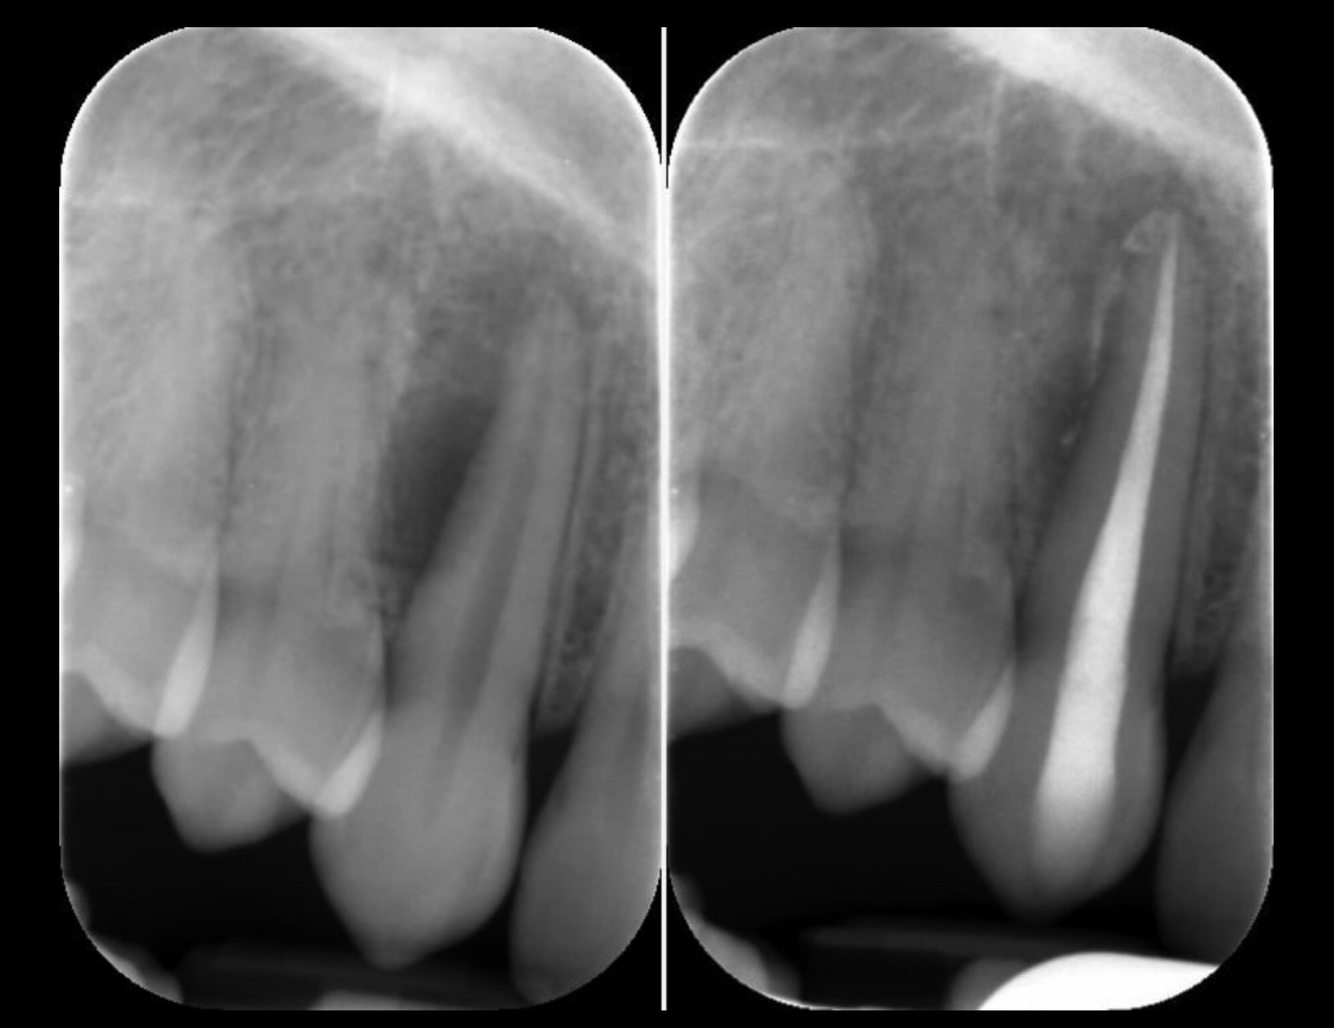

7

Q

Which of these two radiographs belongs to a young individual?

A

Pulp horns are prominent in young individuals